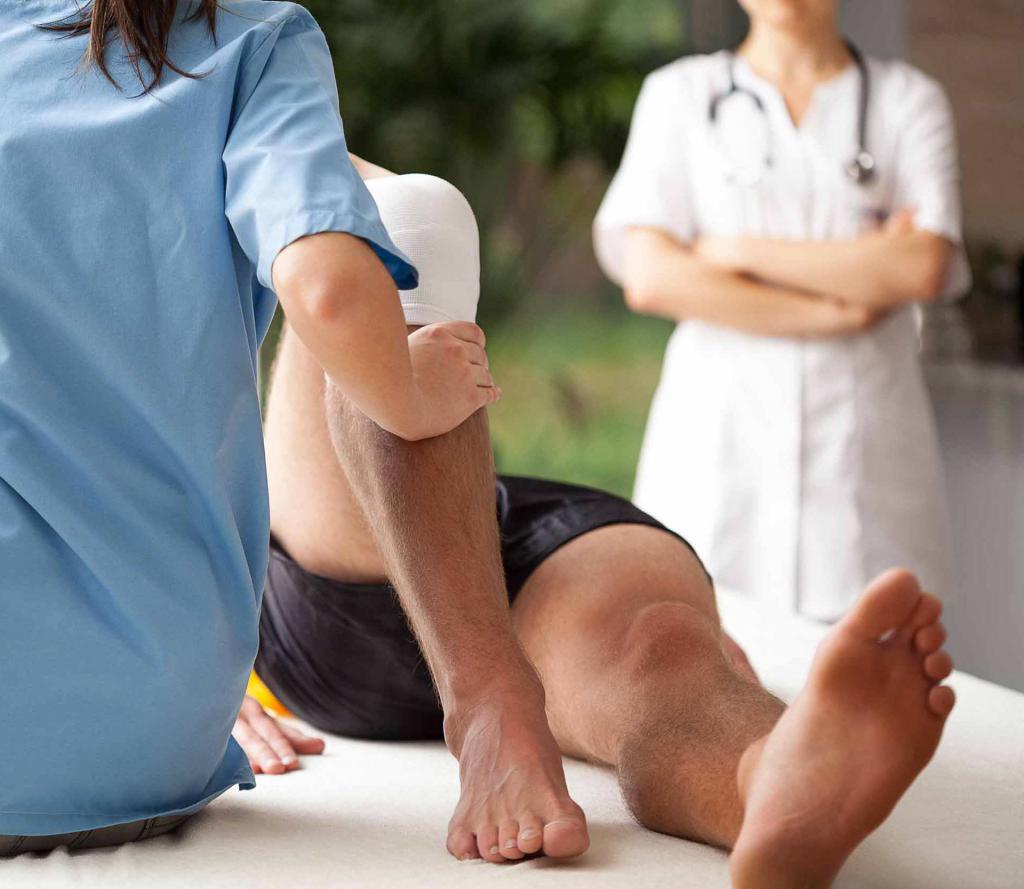

Качественная реабилитация после перелома колена в Беслане недорого и оперативно осуществляется командой опытных и квалифицированных специалистов современного центра восстановления «Исток» с применением эффективных и проверенных методов и технологий воздействия. Нарушение целостности костей, входящих в образование колена чрезвычайно опасно, поскольку может привести к различным негативным последствиям. Они могут появиться на любом из этапов восстановительного периода. Это значительно ухудшит качество жизни человека и приведёт к нарушениям прежнего функционирования конечности.

Качественная реабилитация после перелома колена в Беслане недорого и оперативно осуществляется командой опытных и квалифицированных специалистов современного центра восстановления «Исток» с применением эффективных и проверенных методов и технологий воздействия. Нарушение целостности костей, входящих в образование колена чрезвычайно опасно, поскольку может привести к различным негативным последствиям. Они могут появиться на любом из этапов восстановительного периода. Это значительно ухудшит качество жизни человека и приведёт к нарушениям прежнего функционирования конечности.

Квалифицированные и профессиональные специалисты современного центра реабилитации «Исток» в Беслане по недорогой стоимости осуществляют эффективное восстановление своих пациентов после такого опасного повреждения с применением персонального подхода. Для такой цели мы используем исключительно эффективные методики воздействия, доказавшие результативность на практике. Для такой цели мы первоначально осуществляем обследование пациента, определяем все особенности ситуации и составляем общую клиническую картину. И уже на основании полученных результатов будет составлен оптимальный план восстановления, который позволит достичь максимально продуктивного результата.

Квалифицированные и профессиональные специалисты современного центра реабилитации «Исток» в Беслане по недорогой стоимости осуществляют эффективное восстановление своих пациентов после такого опасного повреждения с применением персонального подхода. Для такой цели мы используем исключительно эффективные методики воздействия, доказавшие результативность на практике. Для такой цели мы первоначально осуществляем обследование пациента, определяем все особенности ситуации и составляем общую клиническую картину. И уже на основании полученных результатов будет составлен оптимальный план восстановления, который позволит достичь максимально продуктивного результата.

Коленный сустав представляет собой самую большую и сложную анатомическую конструкцию, которая обеспечивает широкую амплитуду активной двигательной активности. И в соответствии с получением такой травмы у человека происходит резкое снижение двигательной активности, уменьшается кровообращение и питание, нарушается трофика тканей, что усугубляет тяжести повреждения. Только качественно составленная программа восстановления поможет достичь выздоровления в максимально кратчайшие сроки с возвращением полноценной работоспособности и двигательной активности.

Начинать реабилитацию следует как можно скорее сразу же после устранения сильных болевых ощущений. Обычно это происходит на 2-3 день после получения травмы. И осуществляется такая программа поэтапно. При этом весь процесс может занимать от 4 до 6 недель. Для такой цели вы всегда можете обратиться за помощью в наш частный реабилитационный центр «Исток» в Беслане. Наши специалисты применяют для своих пациентов индивидуальный подход с использованием эффективных методов восстановления.